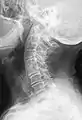

Block vertebrae of the cervical spine (vertebrae 4 and 5). Probably based on degenerative or inflammatory changes.

Several congenital block vertebrae in the transition from the thoracic to the lumbar spine and hemivertebrae.

Congenital block vertebra in the lumbar spine (partial vertebrae 3 and 4). The rear portion of the disc still exists.